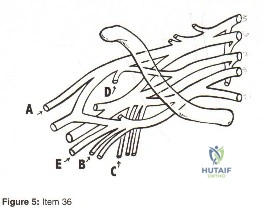

- A

- B

- C

- D

- E